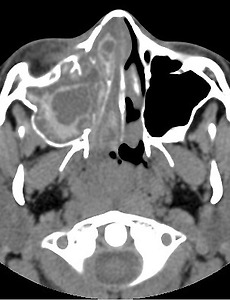

골막하농양(Subperiosteal abscess), 안와농양(Orbital acscess), 해면정맥굴혈전(Cavernous sinus thrombosis) 안와 연조직염(Orbital cellulitis)은, 코곁굴염(sinusitis)눈꺼풀염(blepharitis)눈물주머니염(dacryocystitis)혈행성 전파(hematogenous origin)외상(trauma) 이러한 다양한 원인으로부터 감염이 파급되어 나타나는 대표적인 안와 감염 질환으로 소아에서는 안구돌출의 가장 흔한 원인이 됩니다. 안와 연조직염의 가장흔한 원인은, 코곁굴염, 즉 급성축농증인데, 축농증이 발생한뒤, 염증과 감염이 코의 공간인 부비강에서부터 눈의 공간인 안와 쪽으로 전파되는 것입니다. 이렇게 뼈를 타고 코쪽에서부터 넘어온 감염이, 안와내에 퍼져 있는 것이 안와 연조직염(orbital cellulitis)이고, 안와내로 퍼지지 못하고 안와의 골막하에 고여서 농, 고름이 차는 것이.. 2018. 8. 20.

어린이, 소아에서의 세균성 안와 연조직염, Orbital cellulitis 안와 주위의 감염성 질환은 모든 연령대에서 발생할 수 있고 잠재적으로 시력과 생명을 위협할만한 합병증을 일으킬 수 있는 질환입니다. 특히, 안와 연조직염, Orbital cellulitis 는 항생제의 발달과 적절한 사용으로 잘 치료되어 이로인한 합병증의 빈도는 낮아졌지만, 빠르게 진단하고 적절하게 치료하지 않는다면 실명, 해면정맥굴혈전, 뇌수막염, 경막하축농, 뇌농양과 같은 심각한 합병증을 초래할 수 있습니다. 안와 연조직염, Orbital cellulitis 는 성인에 비해 소아에서 흔하게 발생합니다. 실제로 소아에서 발생하는 안구돌출의 가장 흔한 원인이 바로, 세균성 안와연조직염(bacterial orbital cellulitis)입니다. 하지만 소아 환자들은 증상을 잘 호소하지 못하며 전형적인 증.. 2018. 8. 19.